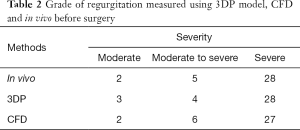

In all patients, the grade of MR and the VCW measured in vitro and in vivo before surgery were highly consistent (Tables 2,3, Figure 6). With the 3DP model, 3 patients were assessed as moderate MR, 4 as moderate-to-severe MR, and 28 with severe MR. Only one patient was assessed as moderate MR in vitro but had moderate-to-severe MR in vivo, and one patient was assessed as moderate-to-severe by CFD but was severe in vivo (Table 2).